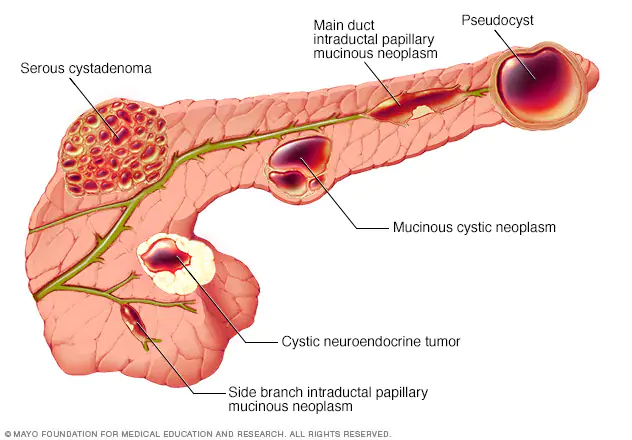

Pancreatic neuroendocrine tumors (pNET) are a group of cancers that can occur in the hormone-producing cells of the pancreas. Pancreatic neuroendocrine tumors, also known as islet cell cancers, are very rare.<br /> Pancreatic neuroendocrine tumors begin in small hormone-producing cells (islet cells) normally found in your pancreas.

Pancreatic cysts are saclike pockets of fluid on or in your pancreas. The pancreas is a large organ behind the stomach that produces hormones and enzymes that help digest food. Pancreatic cysts are typically found during imaging testing for another problem.